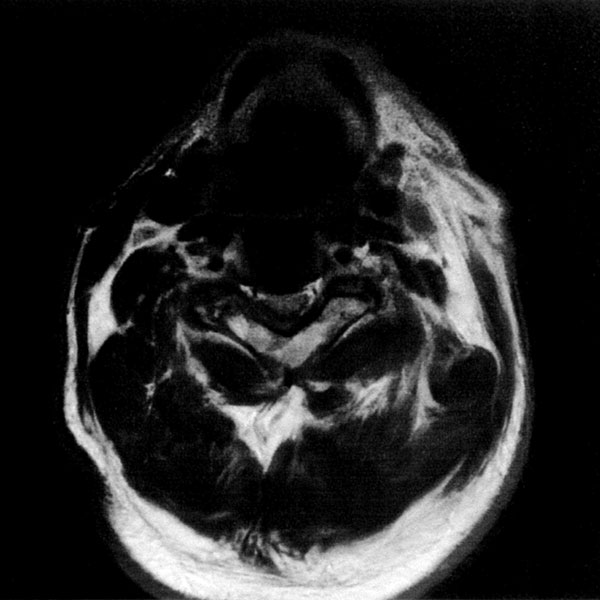

MRI検査

2025年9月16日スタート!!1.5T MRI SIGNA Creator(GE社製)

新しいMRI装置では従来の装置と比較し、高画質、かつ短時間での検査が可能となります。

狭い場所での検査が苦手な方にも優しい設計となっておりますので、検査をしたいけど悩まれている方は一度ご相談ください。

- ラッパ型の開口部:閉所恐怖症の方もご相談ください

- 短時間撮像:医師に相談して10 分弱で検査することも可能です

- AI 機能を搭載:従来の装置と比べかなりの高画質が期待できます

- 従来の装置では難しかった微細な変化の描出にも期待がもてます

- PROPEELR 機能により、動きを抑えたきれいな画像が得られます